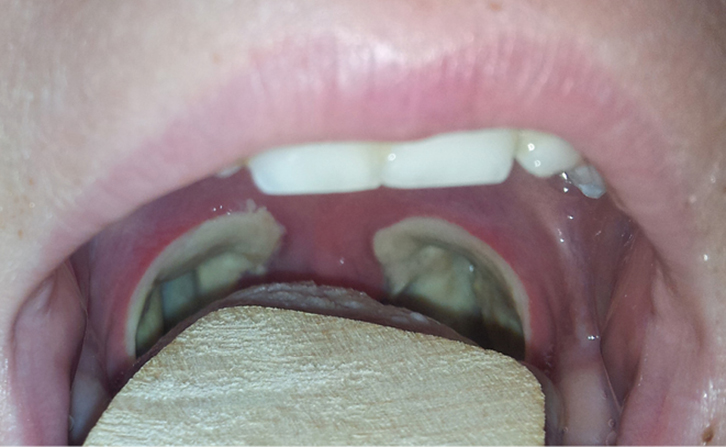

What does the oropharynx look like post operatively? The image below shows what we would expect to see in a normal throat at day 3 and day 10 post operatively.

Day 10.